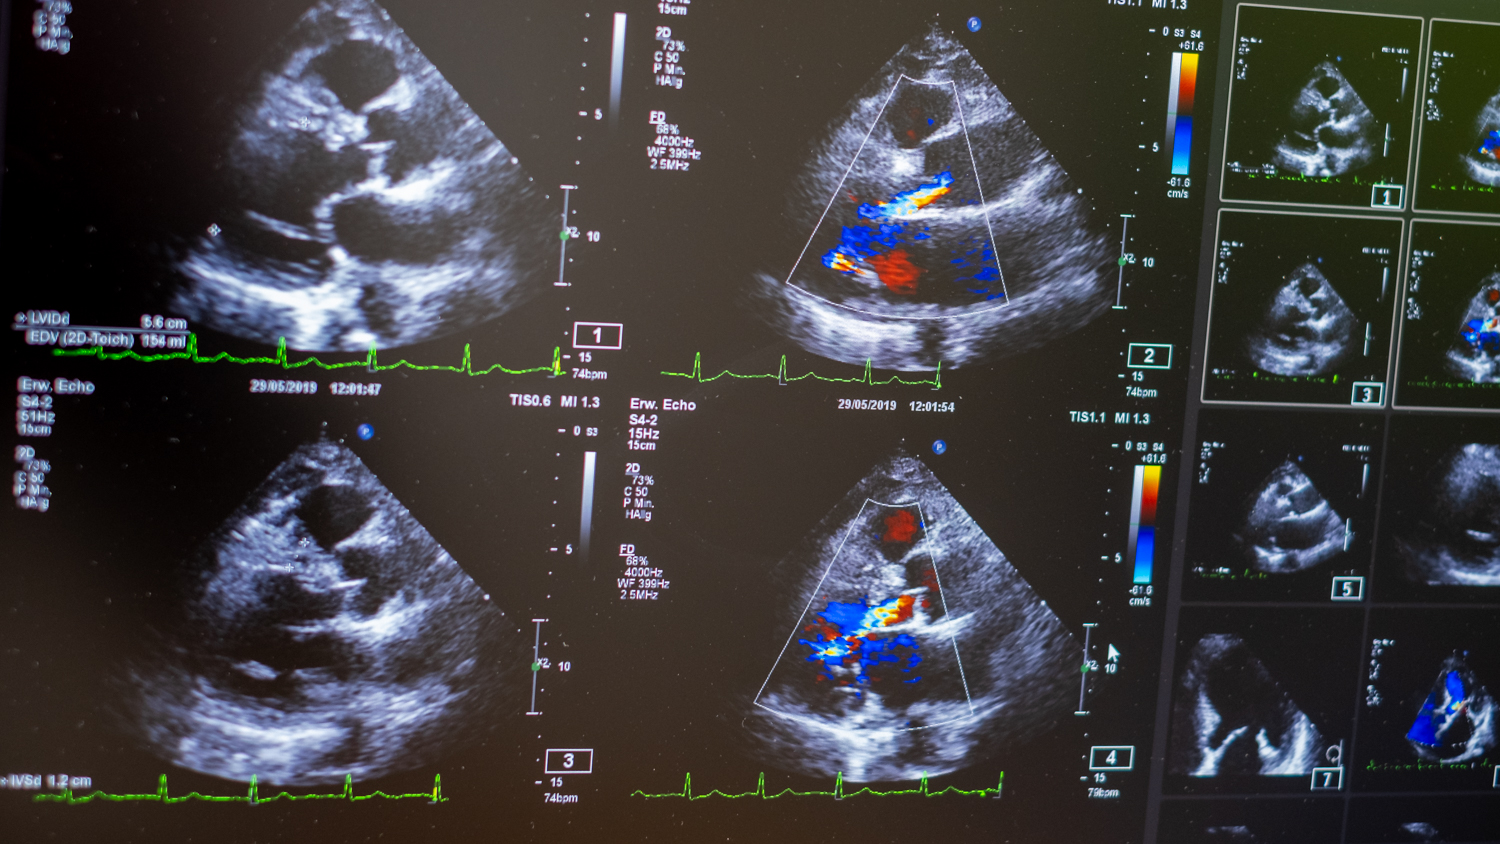

Echokardiographie (Ultraschalluntersuchung des Herzens)

Stressechokardiographie

Technische Ausstattung

Die Praxis verfügt über ein modernes, neues Ultraschallgerät, EKG, Ergometer, Abfragegeräte für Schrittmacher, Eventrecorder und Defibrillatoren sowie Notfallequipment.